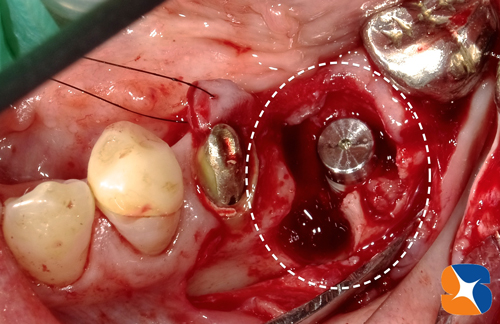

CT撮影での予測通り、ほっぺた側の骨を中心に大きく欠落していました。

この状況の中で、インプラントを的確な位置に、確実に植立します。

同時に、点滴中の患者様のルートより採血させていただきます。CGFと呼ばれる加工細胞を製造して、人工骨と混ぜ合わせ、再び顎骨を回復させていきます。

シュミレーション通り正確にインプラントを植立できました。あとは、骨の欠落部に、CGFと人工骨の一塊をやさしく添加すれば施術は完了です。

〈手術直後の写真〉

この状態のまま、約3ヶ月ほど骨とインプラント体が定着するのを待ちます。

インプラントの周囲にCGFと絡めた一塊の人工骨を添加させます。この人工骨はやがて消失され、本物の骨に置き換わります。